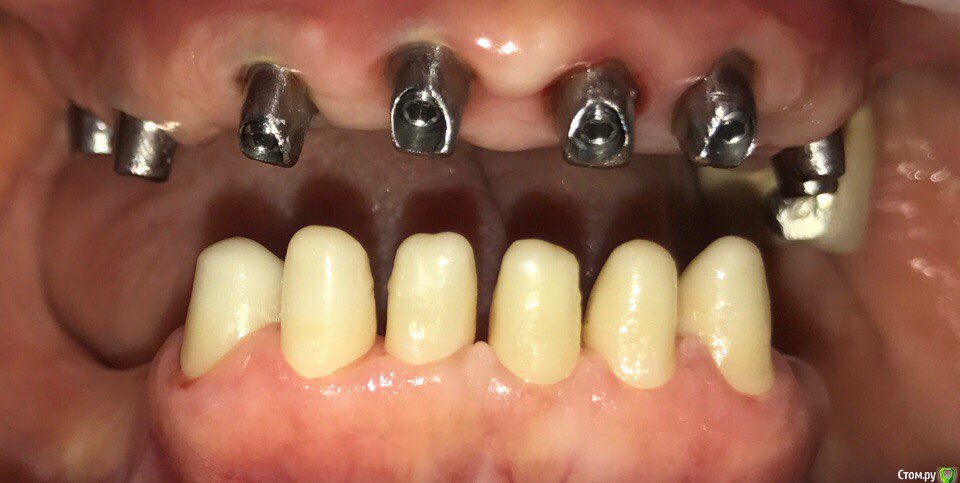

ksenistom Опубликовано 28 мая, 2017 Поделиться Опубликовано 28 мая, 2017 Уважаемые доктора,поделитесь опытом отдаленного протезирования на циркониевой дуге с цементной фиксацией,у меня сейчас сдаётся работа на титановых индивидуальных угловых абатментах,соответственно на них дуга будет фиксироваться. У меня опасения по поводу самой дуги,не будет ли сколов на ней от нагрузки в последствии?И самое страшное,как быть если раскрутится один из винтов в этой конструкции? Ссылка на комментарий

zxc Опубликовано 29 мая, 2017 Поделиться Опубликовано 29 мая, 2017 проведите временное протезирование, установите на нч имплантаты и времянки и только после этого переходите на постоянкуПротяжённые дуги делаю только на металле, он многое прощает )) Ссылка на комментарий

suballex Опубликовано 29 мая, 2017 Поделиться Опубликовано 29 мая, 2017 В смысле,что ко мне пациент пришла когда у неё уже стояли импланты.Система дентиум. Разрезали с целью устранения баланса на дуге,по другому она не досиживалась.А чем Вам не понравились центр. импл?Баланс на ДЦ, это однозначное перепиливание. В смысле - новая фрезеровка. Замыкать верхнюю челюсть жестким материалом - не самая лучшая идея. Правильно боитесь. Выход - первичка из металла, вторичка - ДЦ и одиночки IPS. Или первичка из Тринии + одиночки, они и закроют шахты винтов.Кстати, тут совершенно не нужна подкова.. 1 Ссылка на комментарий